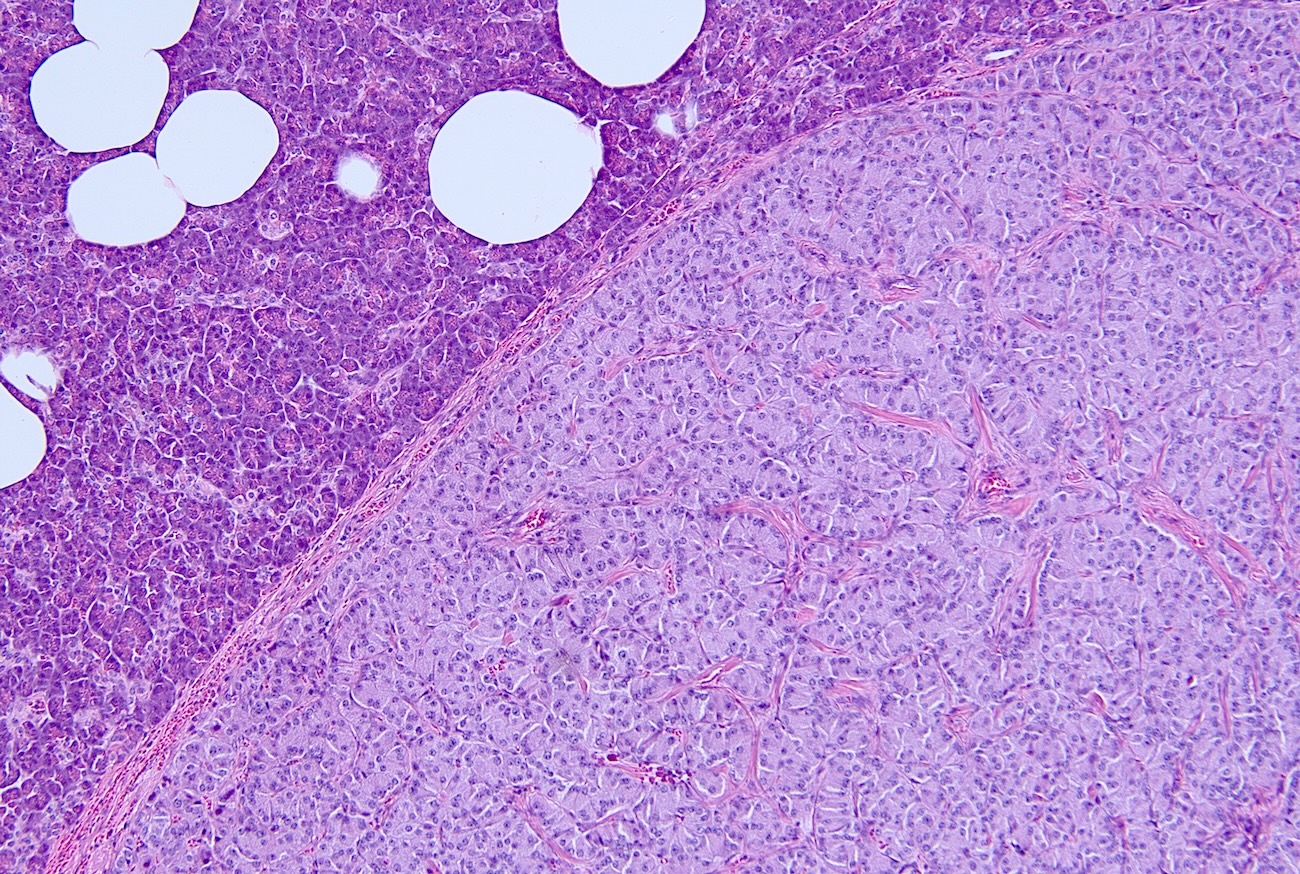

- Parathyroid adenomas / hyperplasia

- Chief cell hyperplasia with a diffuse or nodular growth pattern

- Increased oxyphil cells in some cases (Histopathology 1992;20:305, Surg Pathol Clin 2019;12:1007)

- Loss of fat content in the gland (Histopathology 1992;20:305)

- No significant nuclear atypia but may show monotonous cells with round nuclei and mild anisocytosis (Histopathology 1992;20:305)